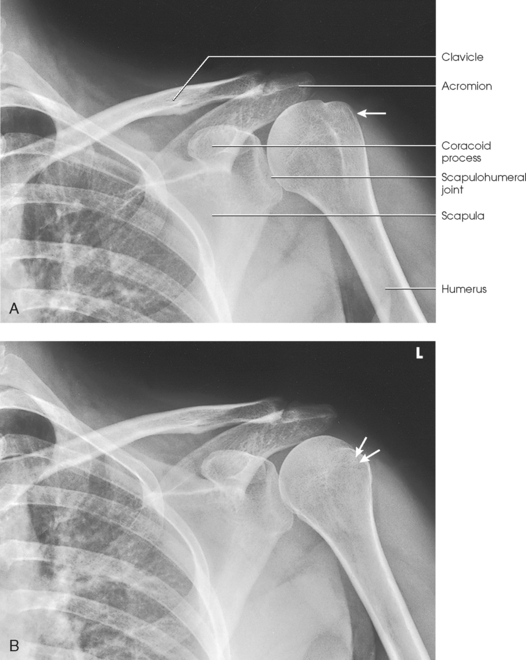

Structures shown: The image shows the bony and soft structures of the shoulder and proximal humerus in the anatomic position (Figs. 5-14 to 5-16). The scapulohumeral joint relationship is seen.

Fig. 5-14 A, AP shoulder, external rotation humerus: greater tubercle in profile (arrow). B, AP shoulder, neutral rotation humerus: greater tubercle (arrow).

Fig. 5-15 AP shoulder, internal rotation humerus: greater tubercle (arrow); lesser tubercle in profile (arrowhead).

External rotation: The greater tubercle of the humerus and the site of insertion of the supraspinatus tendon are visualized (see Fig. 5-14, A).

Neutral rotation: The posterior part of the supraspinatus insertion, which sometimes profiles small calcific deposits not otherwise visualized (see Fig. 5-14, B), is seen.

Internal rotation: The proximal humerus is seen in a true lateral position. When the arm can be abducted enough to clear the lesser tubercle of the head of the scapula, a profile image of the site of the insertion of the subscapular tendon is seen (see Fig. 5-15).